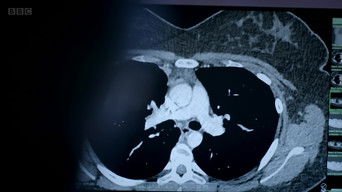

Cameras follow surgeons, anaesthetists, theatre staff and patients at the Queen Elizabeth Hospital Birminghams surgical unit, where surgeons push medical boundaries to the limit.